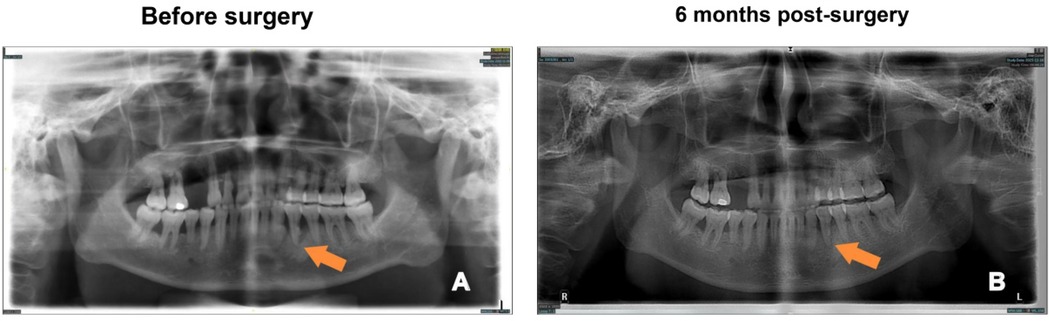

The patient showed significant improvement in clinical condition following periodontal flap surgery. From the initial visit to 6 months post-surgery, the patient's gingival condition exhibited notable changes. At the initial visit (Figure 1A), the patient had considerable gingival edema, deep periodontal pockets, gingival bleeding (BOP+), and plaque accumulation. After basic treatment (Figure 1B), there was a reduction in gingival edema, although some localized disease areas persisted. During the surgery (Figures 1C,D), the affected root surfaces and alveolar bone were successfully exposed, and plaque, calculus, and diseased tissue were meticulously removed. The gingiva was then repositioned and sutured (Figure 1E) to ensure optimal healing, with proper fixation to prevent tension. At 10 days post-surgery (Figure 1F), initial signs of healing were evident, with reduced inflammation and a more normal gingival contour. By 6 months post-surgery (Figure 1G), the gingiva had fully recovered, and alveolar bone loss was effectively controlled, confirming the success of the surgical procedure in restoring periodontal health. In addition to the clinical observations, radiographic images (Figure 2) further demonstrate the improvement in periodontal health. Preoperative radiographs (Figure 2A) revealed significant bone loss and periodontal pockets. However, 6 months post-surgery (Figure 2B), the radiographic images clearly indicate substantial healing, with reduced periodontal pockets and improved bone structure, supporting the positive outcomes of the surgical intervention.

Figure 2. Radiographic comparison of periodontal health before and after surgery. (A) Preoperative radiograph showing the periodontal condition before surgery (arrow indicates the area of concern); (B) Radiograph taken 6 months post-surgery, showing improvement in periodontal health (arrow indicates the healed area).